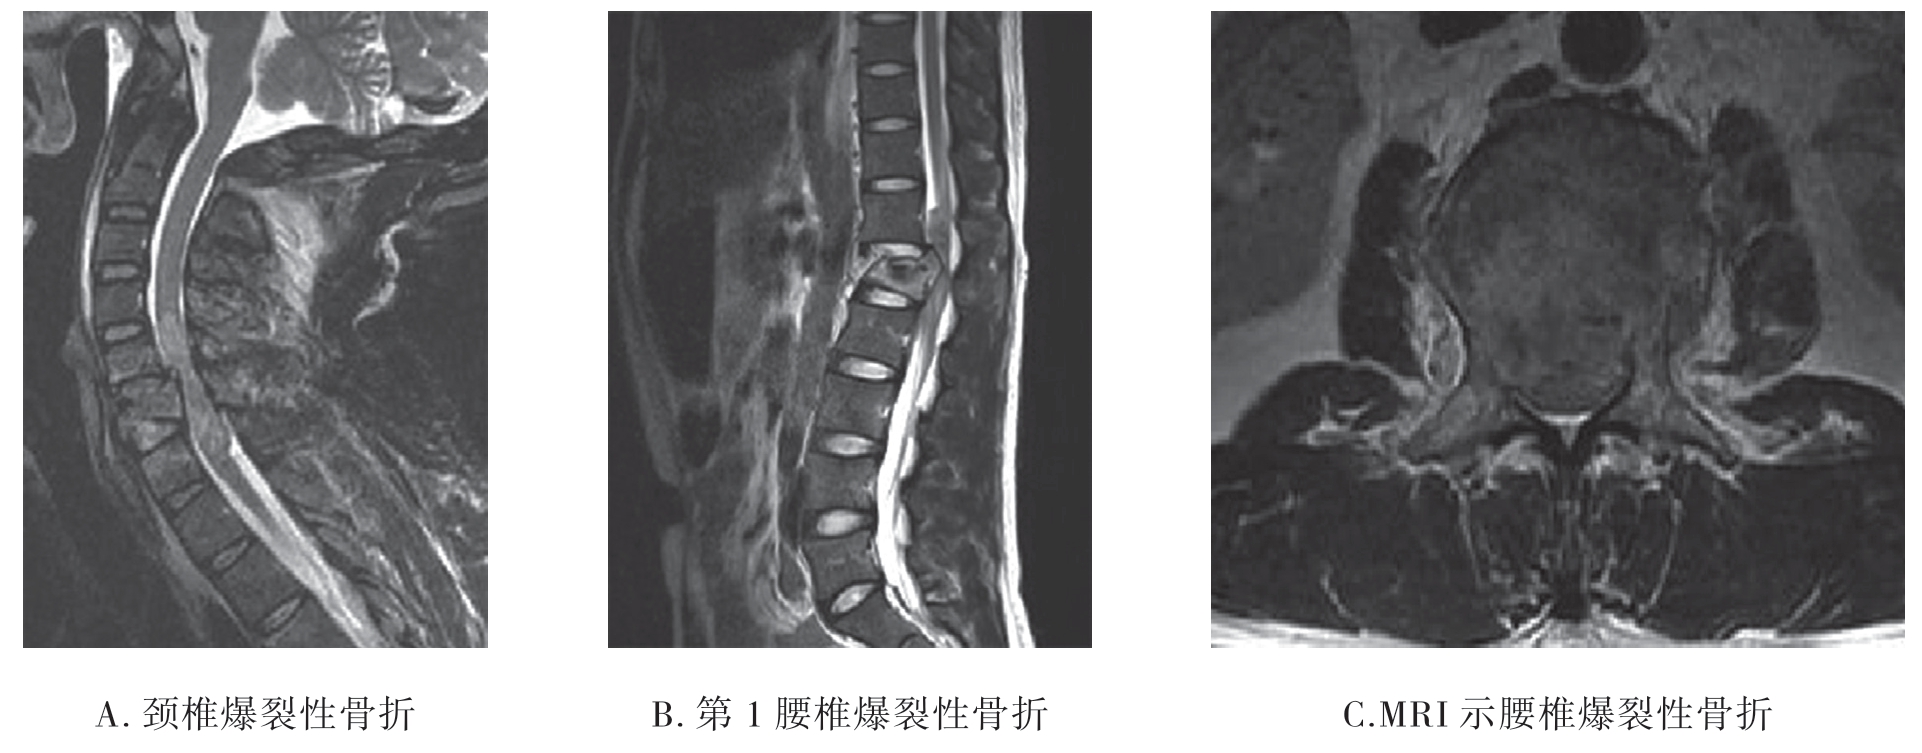

胸腰椎爆裂性骨折主要是受到垂直方向暴力或垂直方向合并屈曲压缩暴力导致椎体破裂,并向四周膨出、移位。

1.X线平片 脊椎受到垂直方向暴力的作用椎体可发生粉碎性骨折。椎体压缩变扁,椎体及附件的骨折片向前后左右各方向移位。X线对爆裂性骨折的显示不如CT检查(图7-2-14)。

图7-2-14 X线平片示腰椎爆裂性骨折

3.MRI检查 MRI能清楚显示脊髓及神经根损伤、韧带、椎间盘及软组织损伤等。损伤的椎体呈粉碎性破裂,椎管断裂、变形;矢状位椎体有不同程度移位,椎间盘破裂并移位,骨折脊椎成角畸形;急性期损伤的脊椎均伴有骨挫裂伤,相邻的脊髓受压变形(图7-2-16)。

图7-2-16 MRI示爆裂性骨折